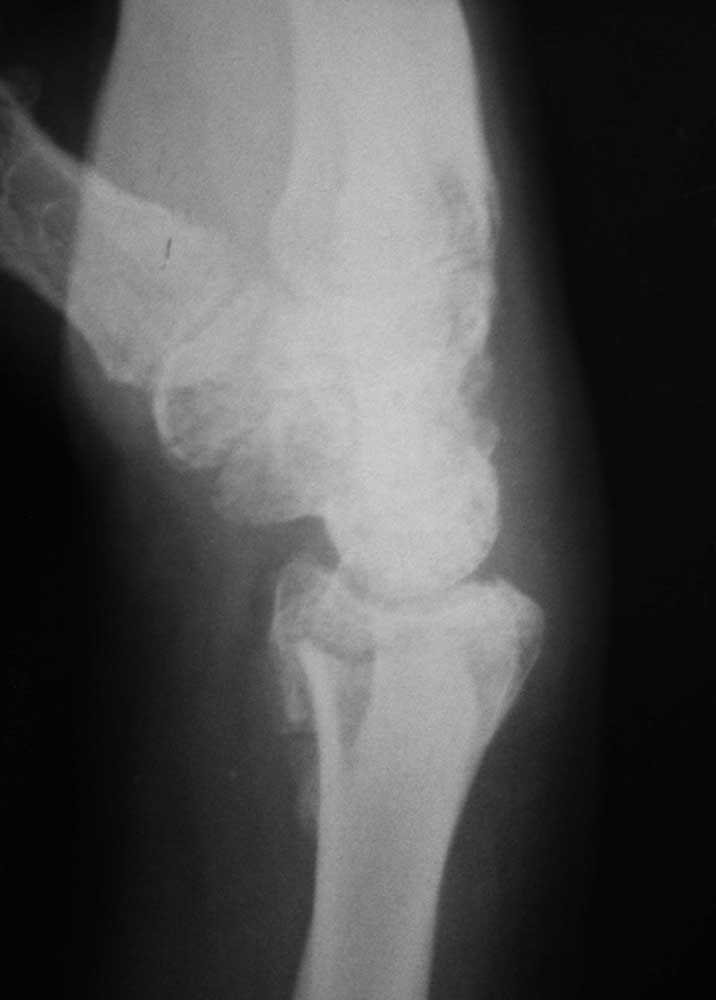

То же самое, только в профиль

Как я понял, срок иммобилизации составил 3 месяца! Описанная Вами функция лучезапястного сустава (странно, что не указана функция кисти) вполне соответствует этому. Дальше нужно определиться что лечить: рентгенограмму или больного. В первом варианте оправдано выполнение корригирующей остеотомии с костной аутопластикой. Выбор фиксации, ЧКДО или locking plate, зависит от Ваших предпочтений. В итоге получите красивую ретгенкартинку и кисть с функцией ласты. Плавать будет быстро.

мне кажется, можно попробовать дозированное исправление деформации в аппарате. Учитывая сроки, остеотомия на уровне "шипа" дистального отломка, выращивание трапециевидного регенерата.

На практике в ближайшшее время (6 мес.) было выполнено 4 операции у пациентов с подобной патологией, правда срок давности в основном 2 месяца и меньше. Большей причиной для выполнения операции, все-таки было дастаточно значительное угловое смещение в боковой проекции или наличие осколков, ограничивающих функцию. С учётом анамнеза травмы (кататравма, 5 этаж) мне кажется, что коллеги правы склоняясь в сторону консервативного разрешения вопроса. Я думаю, что при такой траме есть более серьёзные вопросы по реабилитации. Михаил. г. Йошкар-Ола.